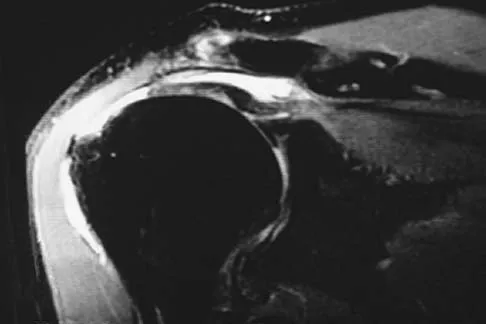

Question 43

An 80-year-old man has had increasing shoulder pain for the past 4 months. He reports that it began with soreness and stiffness after chopping some wood. A coronal MRI scan is shown in Figure 16. Initial management should consist of

Explanation